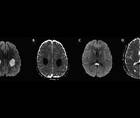

Recurrent Stroke-Like Events Before Diagnosis of X-Linked Charcot—Marie—Tooth Disease